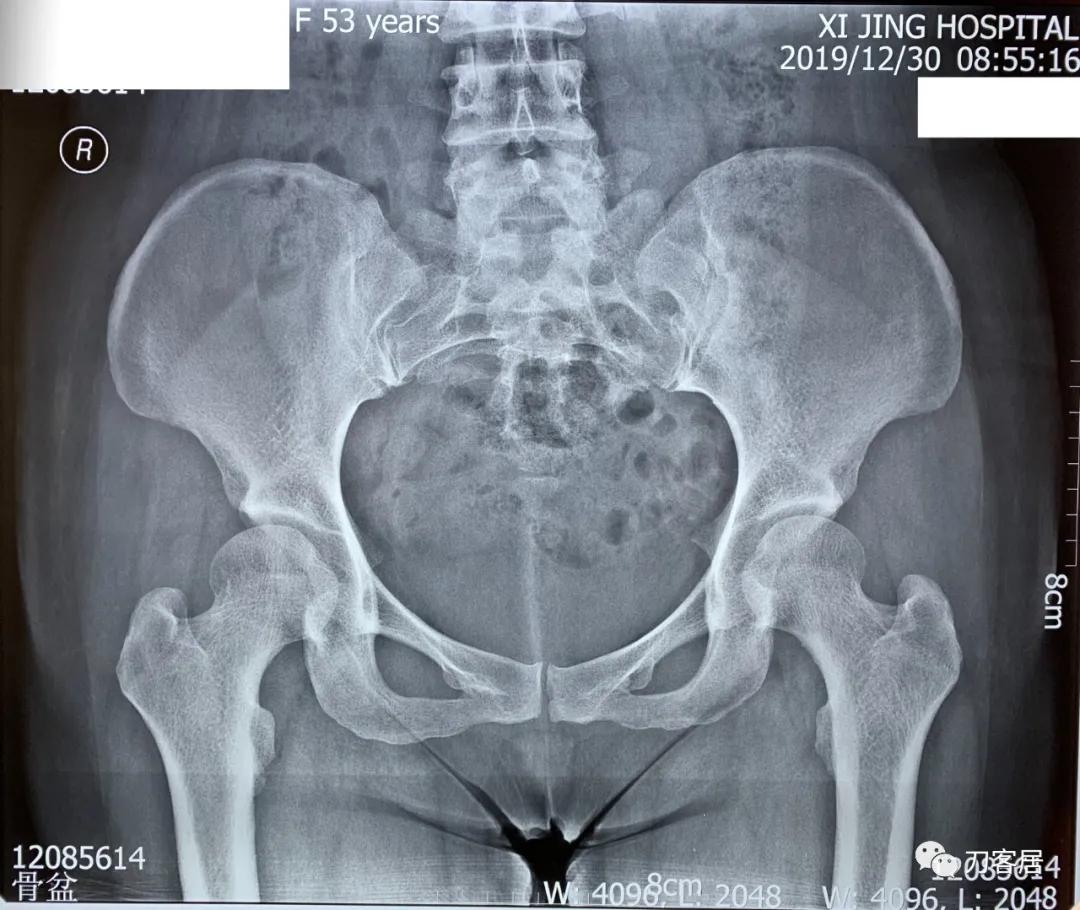

自带腰骶椎MRI提示骶管囊肿术后改变,已与患者及家属讲明骶管囊肿常用的手术方式以及较高复发率的可能性。骨盆平片提示双侧髋臼发育不良,髋臼发育陡浅,尤以右侧为重。

20191230-西京医院骨盆X线平片

诊断: 双侧髋臼发育不良, 骶管囊肿术后。